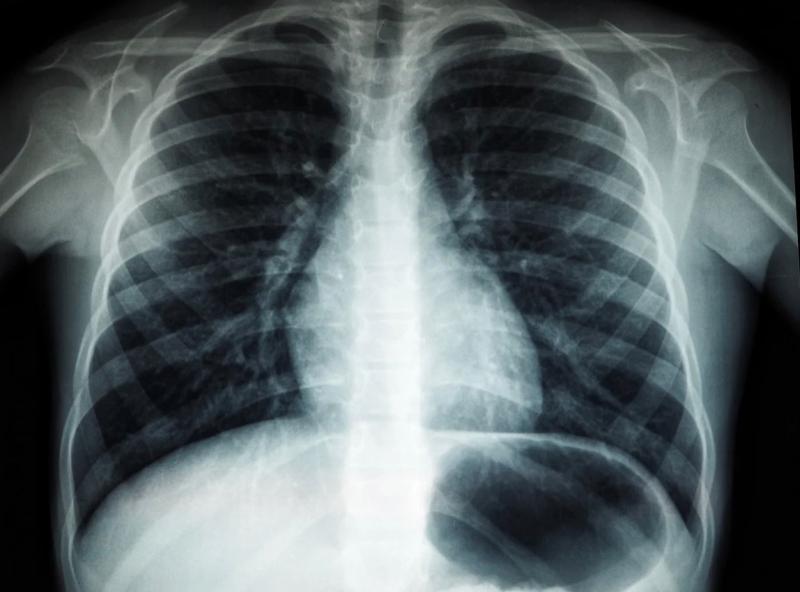

Минздрав: ранняя диагностика и скрининг - самая эффективная профилактика рака легких

Директор НМИЦ онкологии им. Н. Н. Петрова Минздрава России Алексей Беляев подчеркнул: сейчас в стране уже существует и теоретическая основа, и практические примеры реализации подходов к ранней диагностике рака и скринингу. И в данный момент ведется масштабная работа по налаживанию маршрута пациента после выявления проблем с легкими.

Врач уверен, что важно в этом вопросе более детально подходить к развитию цифровизации российского здравоохранения и создать единую информационную систему. Это поможет быстрее поставить точный диагноз человеку и приступить к необходимому лечению.